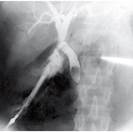

Больная, 58 лет, длительное время страдала ЖКБ. В анамнезе - желтуха, возникшая после приступа. На операции при холангиографии выявлена следующая картина (рис. 68). Диаметр холедоха 18 мм.

Ваш диагноз? Дальнейшая тактика?

Рис. 68. Холангиограмма больной, 58 лет